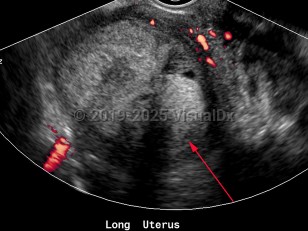

Endometrial carcinoma

Endometrial carcinomas are more common in women of European descent and more likely to develop after menopause.